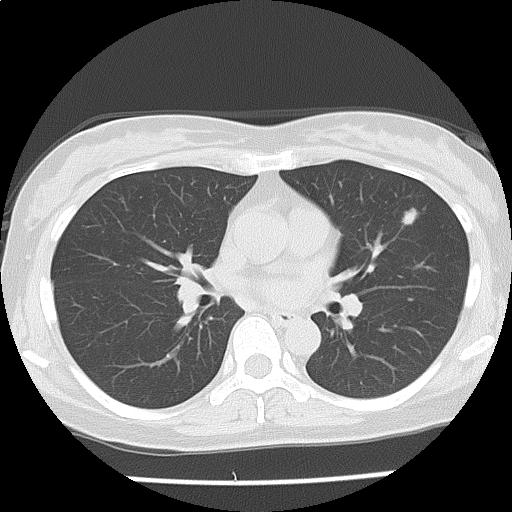

両肺に径数 mm~約9 mm の結節が多発しており(添付画像以外にも認める)、辺縁不整を認める。

多発肺転移の可能性をまず除外する必要があり、原発としては乳癌、膵癌などと考える。

悪性が否定的な場合には、感染症、血管炎、サルコイドーシスなども鑑別に挙げられる。

多発肺結節・縦隔リンパ節腫大:r/o 多発肺転移